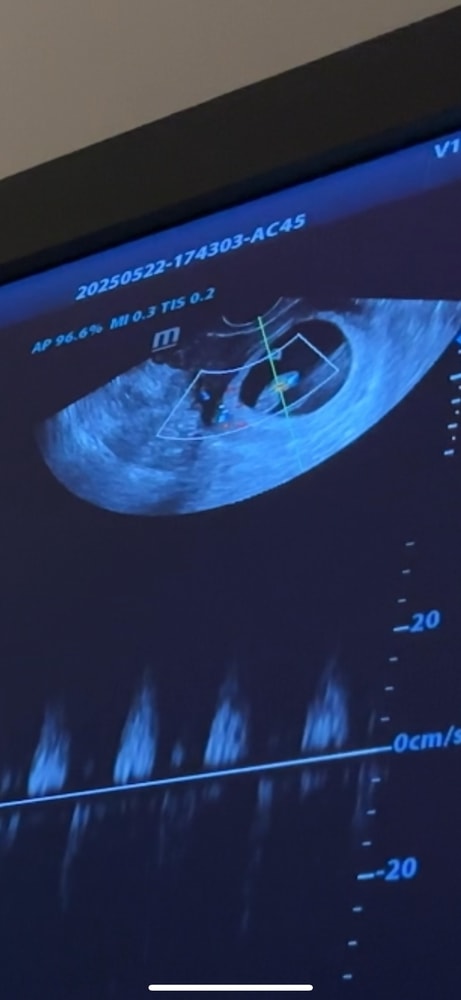

Диана, сейчас кстати поискала узи со вторым сыном ,срок правда поменьше ,с ним совпадает с картинкой выше 😁 Изображение